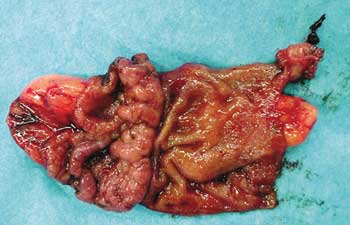

O pós-operatório transcorreu sem

anormalidades e o paciente recebeu alta no 2º dia de

pós-operatório. O exame anatomopatológico

confirmou que a peça operatória tratava-se de divertículo

de Meckel com a presença de mucosa gástrica

ectópica e sinais de hemorragia (Figura 4).

| Figura 4 _ Peça operatória aberta. |